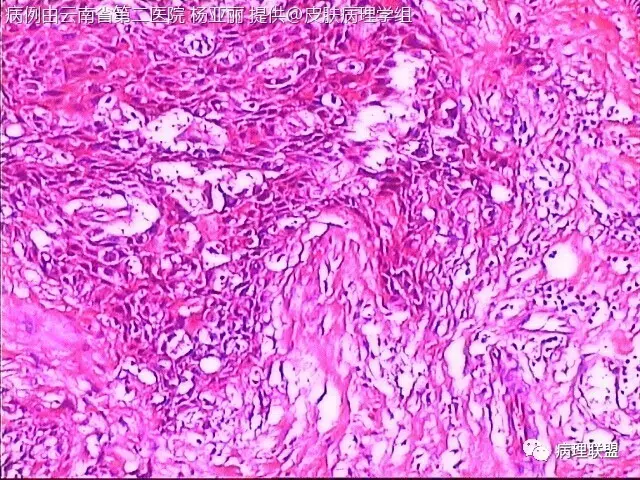

M/53 左手食指包块(皮肤鳞癌VS转移性鳞癌)

请各位老师帮忙看看,男性,53岁,左手食指包块 (病例由云南省第二医院 杨亚丽 提供,致谢!)

鳞癌没有问题。问题是否是转移癌:有否与表皮相连,病史演变如何?

@邓永键 谢谢邓主任,据说病人鼻子上有肿瘤才来切的手上的小包块,右手有,左手也有三四个,等我再问问鼻子上的是什么。看着细胞异型不明显,生长方式倒是确实不好。第6图有和表皮的关系,不相连,邓老师,鼻子上的肿瘤确实是鳞癌,这么说来手上的是转移的就很合理了。邓主任真是高,佩服!